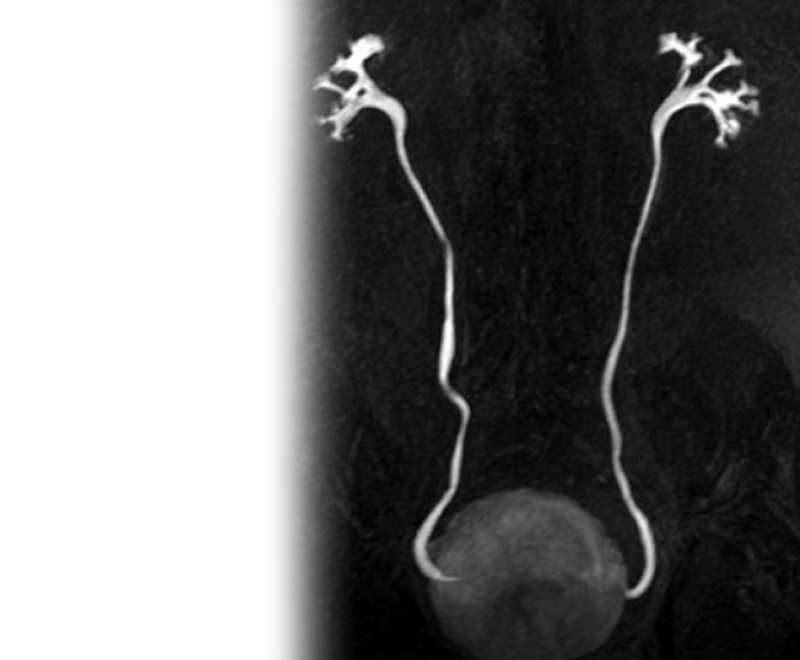

МР бесконтрастная урография

МР бесконтрастная урография – важный метод исследования, который позволяет оценить состояние мочевыводящих путей без введения контрастного вещества.